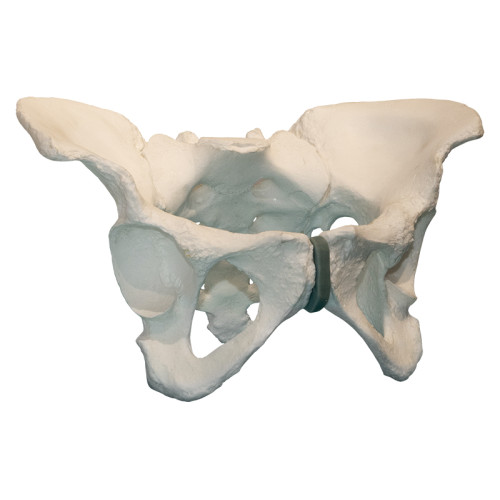

Композитная модель таза

Композитная модель таза

Описание

Модель представляет точную анатомическую копию таза человека. Путем подбора полимерных материалов механические свойства изделия (вес, плотность, упругость) максимально приближены к естественным прижизненным значениям.